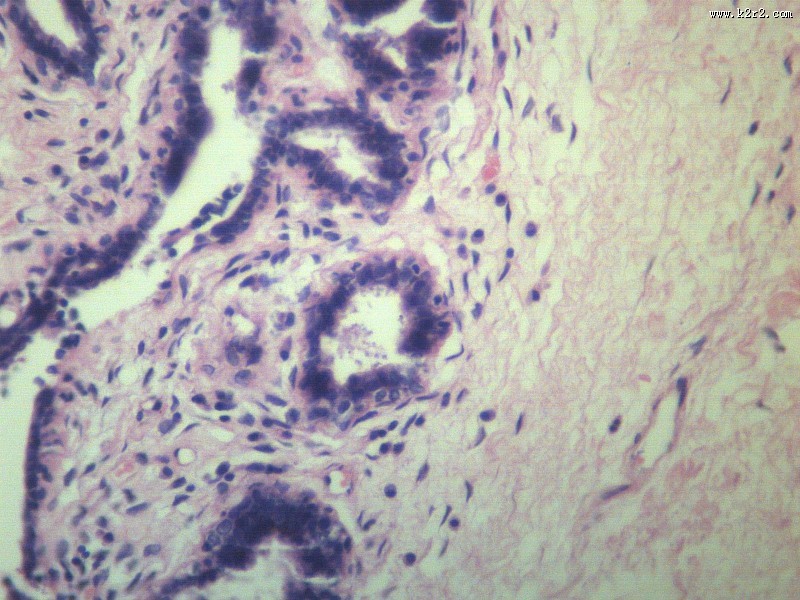

乳腺纤维腺瘤 - 第6张

乳腺纤维腺瘤

fibroadenoma of breast

肿瘤显微切片